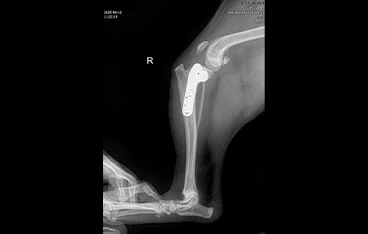

• THR

• THR 전

THR 후